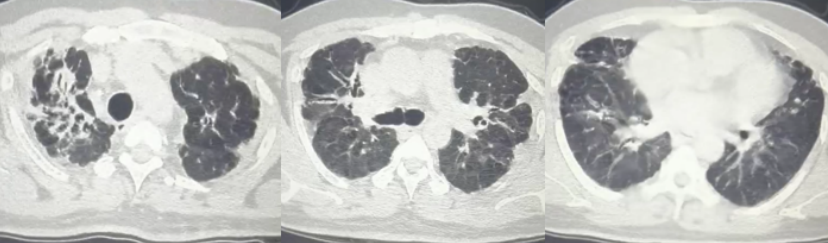

诊断为“肺炎,支气管扩张”,予抗感染治疗2周并加用甲强龙治疗(图3)。咳嗽、喘息明显减轻出院,继续口服醋酸泼尼松15 mg qd(11月13日-12月7日,24 d)。

11月10日(激素治疗12 d)复查胸部CT:双肺斑片影、结节影、磨玻璃影较前吸收(图4)。